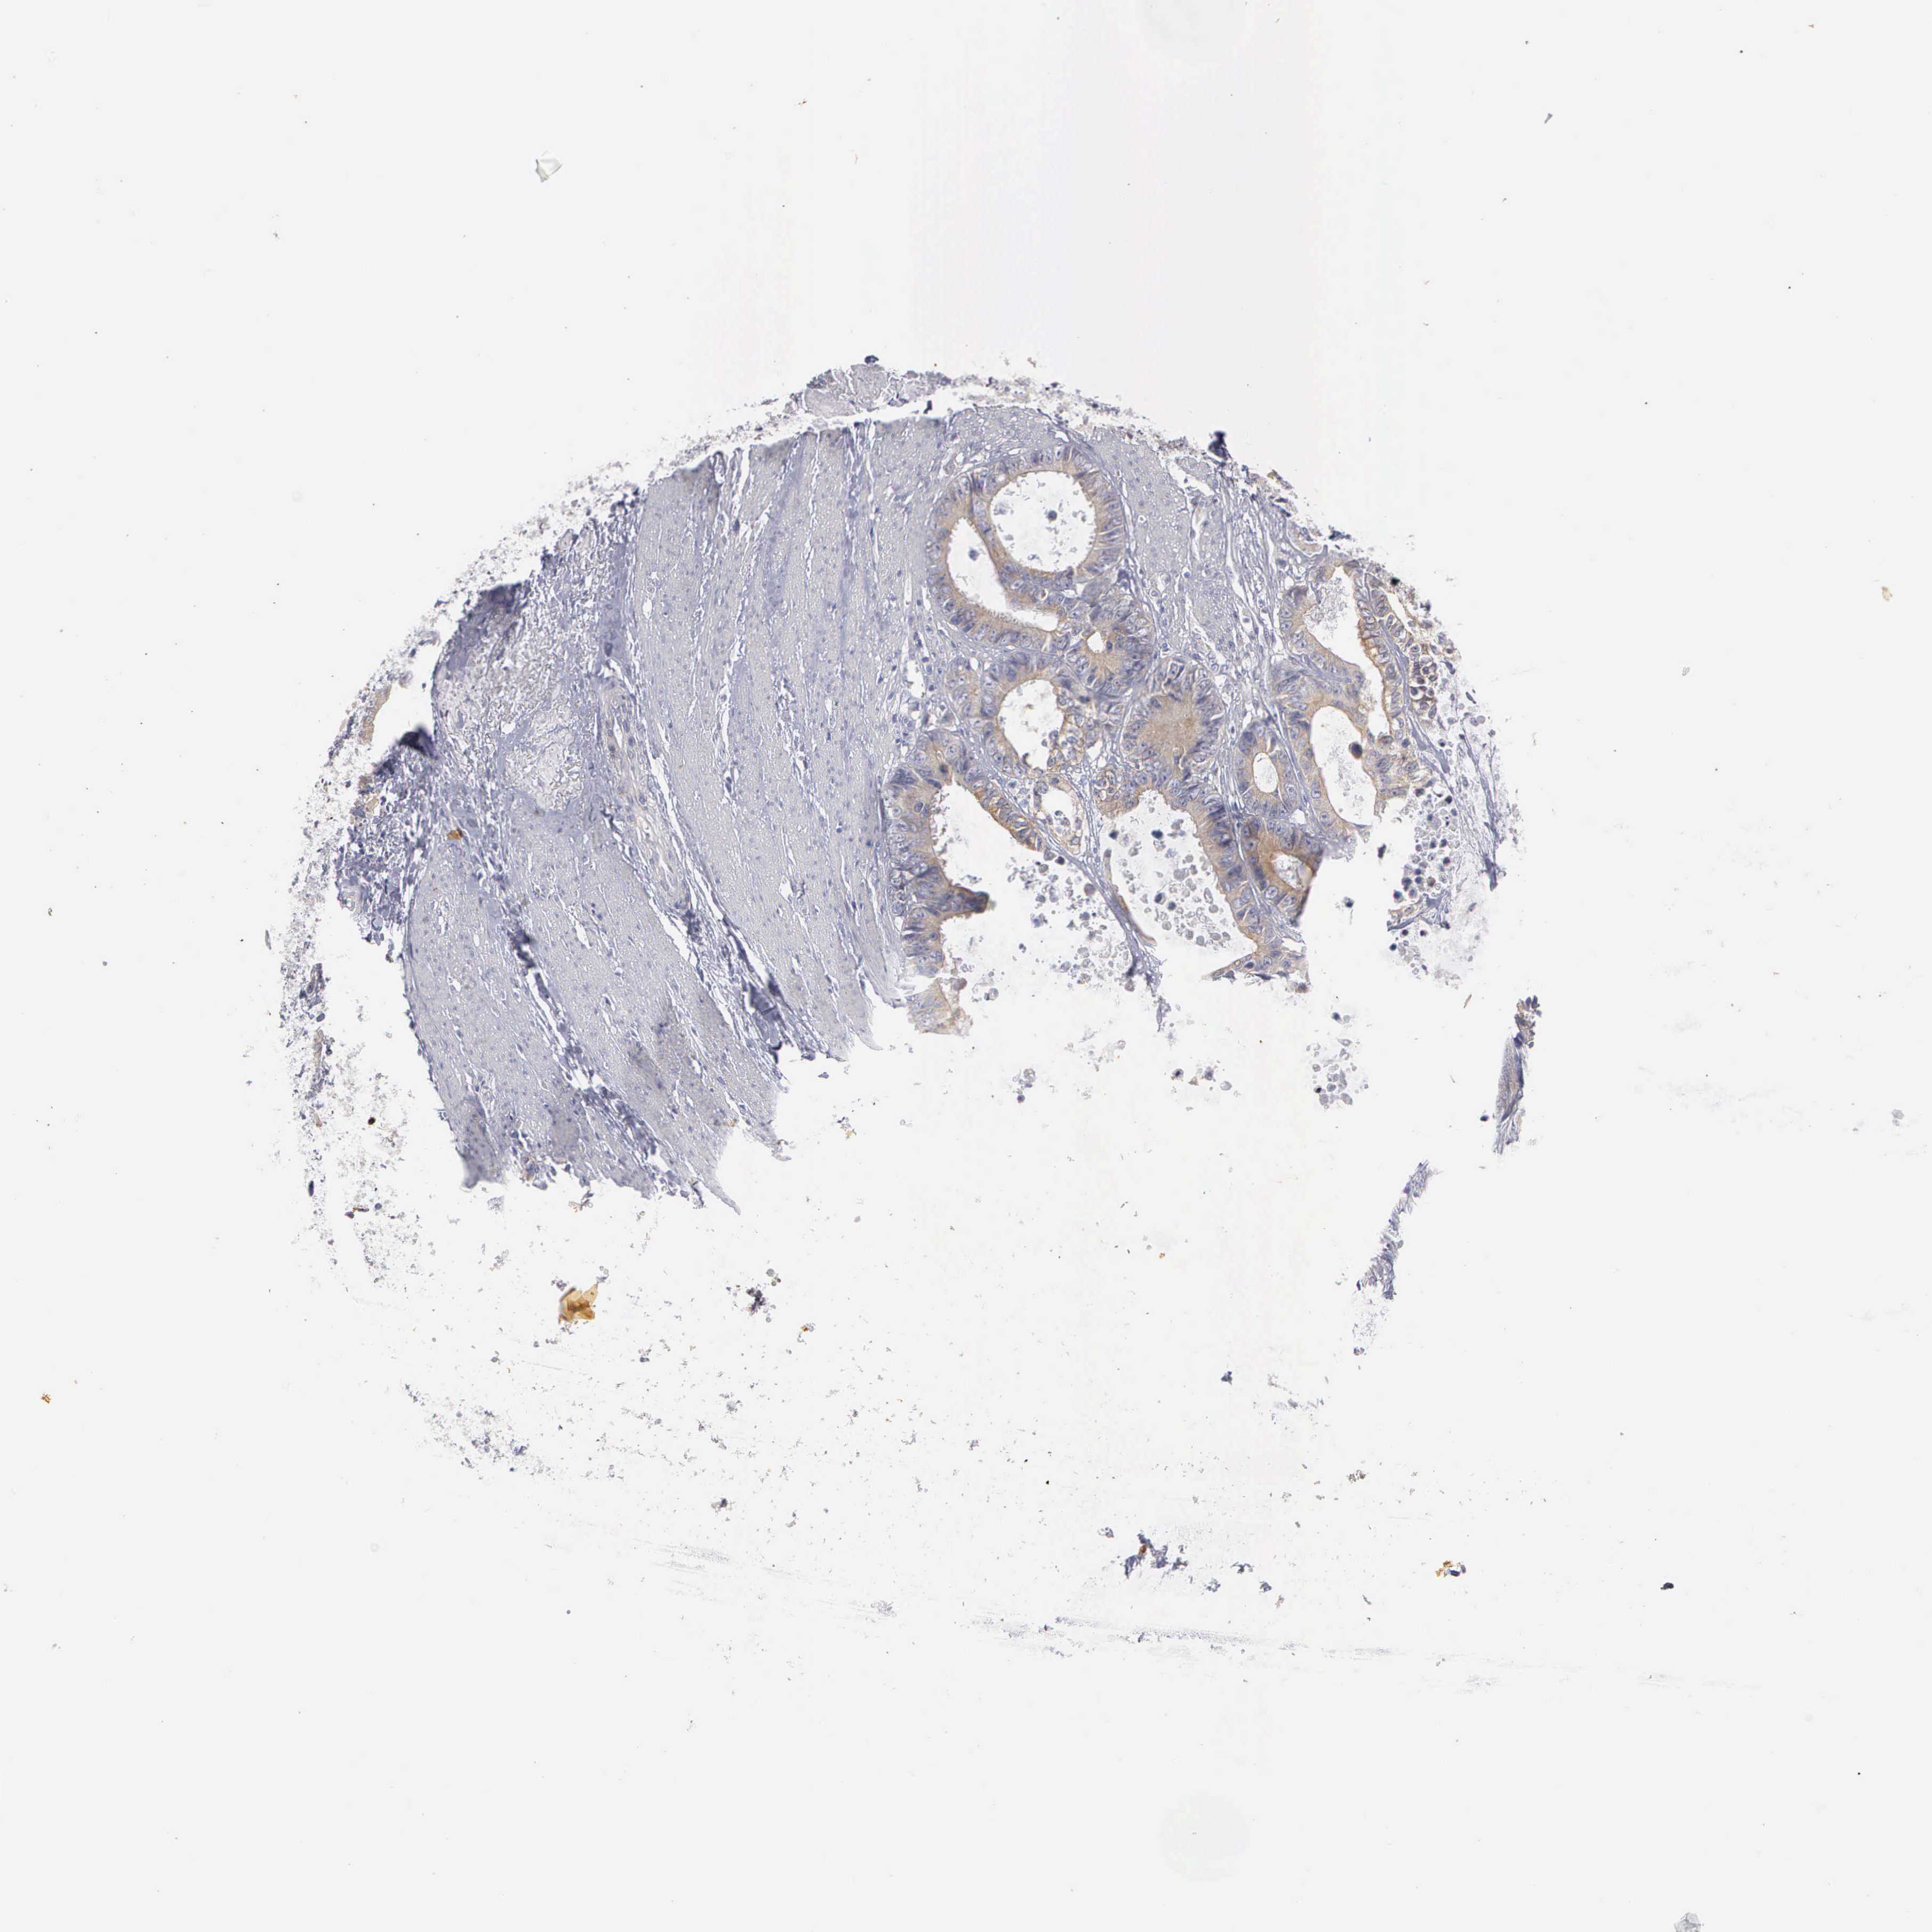

CANCER COLORECTAL CANCER Show tissue menu

Colorectal cancer

Human cancer

Colon adenocarcinoma